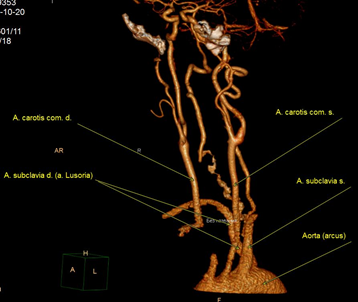

В послеоперационном периоде проводились дополнительные исследования – по данным ангиографии и компьютерной томографии подтверждено наличие сосудистой аномалии в виде a. lusoria. Послеоперационный период у больной протекал гладко, без осложнений. Фонация голосовых связок не была изменена. Проведенные дополнительные исследования подтвердили наличия a. lusoria. По данным МСКТ-ангиографии правая подключичная артерия (a. lusoria) отходит отдельным стволом позади и левее от места отхождения левой подключичной артерии, расположение ее предпозвоночное позади пищевода, отмечается сдавление пищевода (рис. 6 а, б, в).

Рис. 6. Результаты рентгенологического исследования: а – МСКТ расположения a. lusoria; б – компьютерная ангиография (вид спереди); в – компьютерная ангиография (вид сзади).

По данным ангиографии – ангиографическая картина a. lusoria. Справа налево от дуги аорты отходят устья правой и левой общих сонных артерий, левой подключичной артерии и правой подключичной артерии (последние два практически на одном уровне) (рис. 7).

Рис. 7. Ангиография.